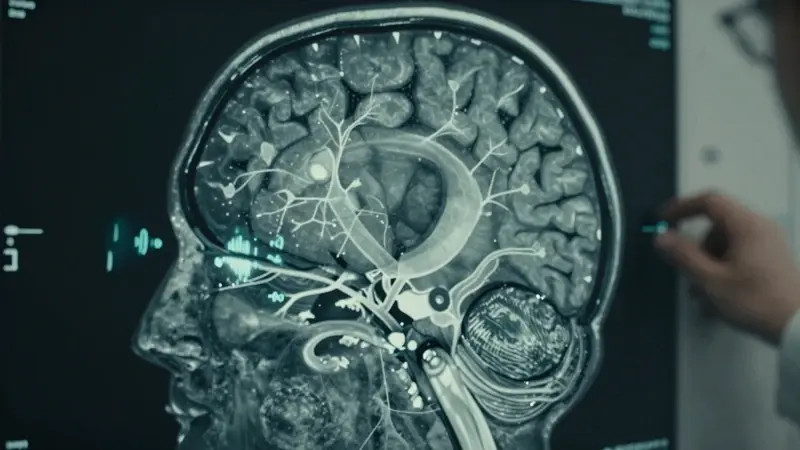

Por Qué se Escapan los Sueños: La Neurociencia del Olvido Onírico

La dificultad para recordar los sueños no es un fallo de memoria, sino una consecuencia de cómo funciona nuestro cerebro durante el sueño. Durante la fase REM (Movimiento Ocular Rápido), cuando la mayoría de los sueños ocurren, algunas áreas cerebrales clave para la consolidación de la memoria a largo plazo se encuentran relativamente inactivas. En particular, el hipocampo, crucial para la formación de nuevos recuerdos, y la corteza prefrontal, implicada en la organización y el procesamiento de la información, tienen una actividad reducida. Esto significa que, aunque tu cerebro esté muy activo generando imágenes y narrativas oníricas, no está "grabando" esas experiencias de la misma manera que lo hace durante la vigilia.

Además, la naturaleza fragmentada, simbólica y a menudo ilógica de los sueños dificulta su almacenamiento en la memoria a largo plazo. El cerebro prefiere consolidar recuerdos coherentes y significativos, y los sueños, con su flujo libre de asociaciones y alteraciones de la realidad, a menudo no cumplen con estos criterios. Un estudio publicado en Science sugiere que la memoria a corto plazo es prominente durante la fase REM, pero tiene una capacidad limitada y solo dura unos 30 segundos. Si no nos despertamos durante ese breve lapso, el sueño simplemente se disipa.